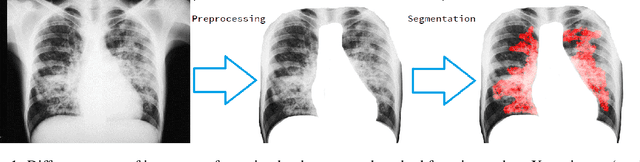

Abstract:Unets have become the standard method for semantic segmentation of medical images, along with fully convolutional networks (FCN). Unet++ was introduced as a variant of Unet, in order to solve some of the problems facing Unet and FCNs. Unet++ provided networks with an ensemble of variable depth Unets, hence eliminating the need for professionals estimating the best suitable depth for a task. While Unet and all its variants, including Unet++ aimed at providing networks that were able to train well without requiring large quantities of annotated data, none of them attempted to eliminate the need for pixel-wise annotated data altogether. Obtaining such data for each disease to be diagnosed comes at a high cost. Hence such data is scarce. In this paper we use contrastive learning to train Unet++ for semantic segmentation of medical images using medical images from various sources including magnetic resonance imaging (MRI) and computed tomography (CT), without the need for pixel-wise annotations. Here we describe the architecture of the proposed model and the training method used. This is still a work in progress and so we abstain from including results in this paper. The results and the trained model would be made available upon publication or in subsequent versions of this paper on arxiv.